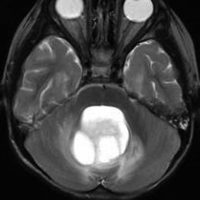

同じような小児例です

右側は手術直後のFLAIR像です。小児ですから大きなのう胞はすぐに潰れて小脳がもどります。白質損傷もなく腫瘍は摘出できています。